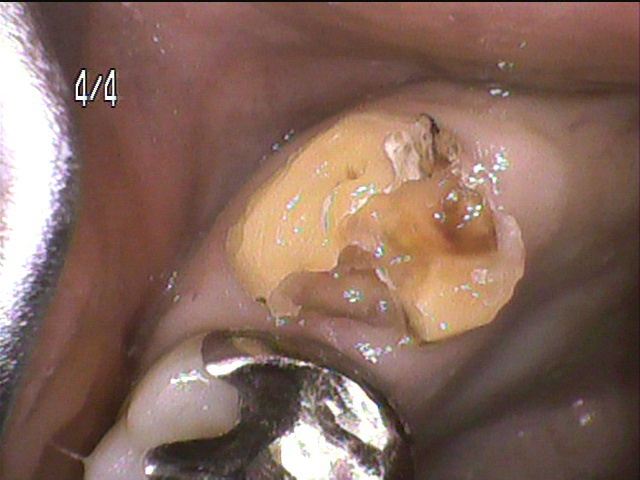

治療中写真

- 金属を外して虫歯の部分を除去すると、髄腔に達していました。

神経を取って、根っこの治療を行いました。